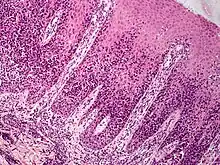

Pagetoid reticulosis (also known as "acral mycoses fungoides",[1] "localized epidermotropic reticulosis",[1] "mycosis fungoides palmaris et plantaris",[1] "unilesional mycosis fungoides",[2] and "Woringer–Kolopp disease"[1]) is a cutaneous condition, an uncommon lymphoproliferative disorder, sometimes considered a form of mycosis fungoides.[1]: 734

Lesions emerge as well-demarcated psoriasiform or hyperkeratotic patches and plaques, with a central clearing and an elevated border.[3] Pagetoid reticulosis is a very slow progressive variant of mycosis fungoides and is usually localized unlike the latter.[4]